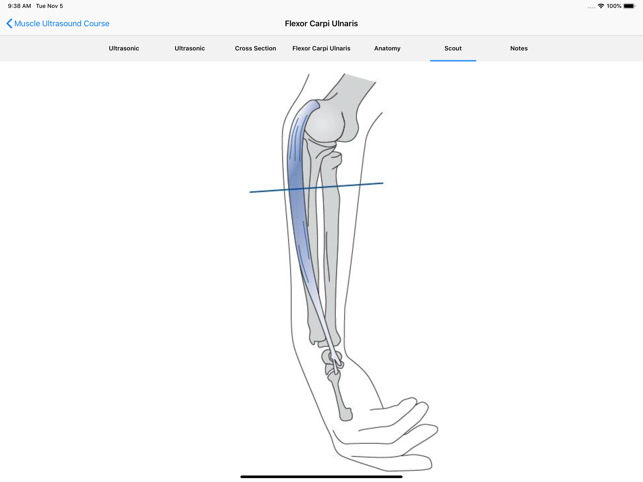

• Improve your skills in identifying muscles and neighbouring structures using ultrasound! • Instructive ultrasound cross-sectional images and videos• Plus: cross sections, scouts and the option for individual annotations• Use it as a Point-of-care APP on your smart phone or as a reference APP for anatomical studies. • Online content for quick reference and updates. Download option for permanent availabilityEntwickler App: Quickbird Studios GmbH, www.quickbirdstudios.comEntwickler Content: Child & Brain GmbH, www.childandbrain.com